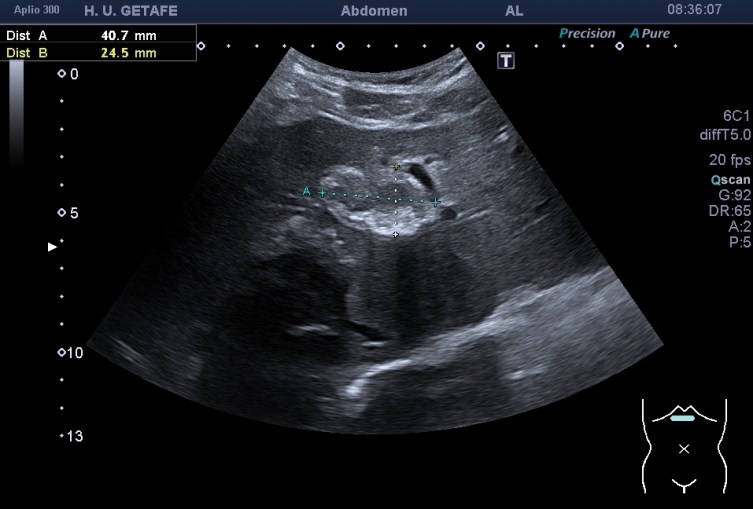

Durante la exploración de una eco de abdomen en el contexto de un paciente que acude por elevación de transaminasas observo una imagen heterogénea, irregular, con una pared marcadamente calcificada, bilobulada de gran tamaño que medí en dos partes ya que me pareció claramente que estaban diferenciadas.

Una de ellas, la primera, era mucho más hiperecogénica y más pequeña, su centro estaba mas calcificado, su sombra acústica posterior era mucho más acuciada y llamaba más la atención. Justo al lado, otra lesión de mayor tamaño, su calcificación era mucho más sutil y más periférica delimitando una LOE hipoecogénica de un tamaño muy importante, adyacente a la más pequeña, como he comentado previamente. Ambas sin señal Doppler.